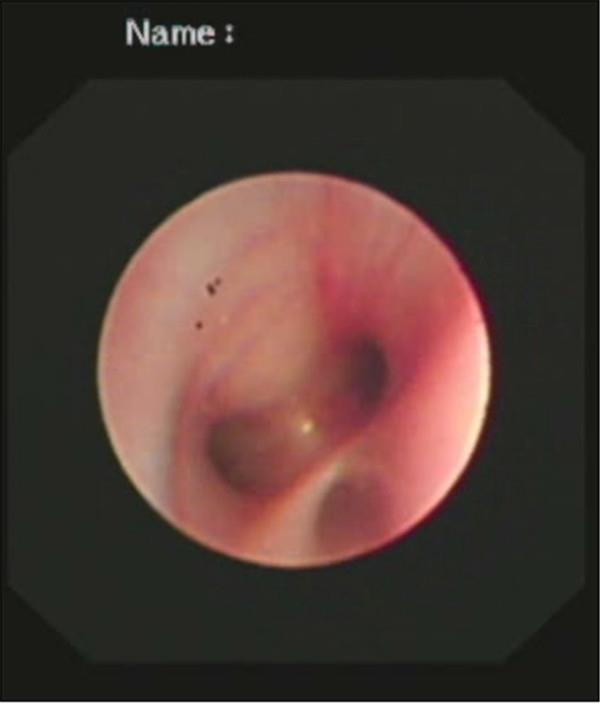

支氣管鏡檢查中

檢查中氣道內(nèi)情景